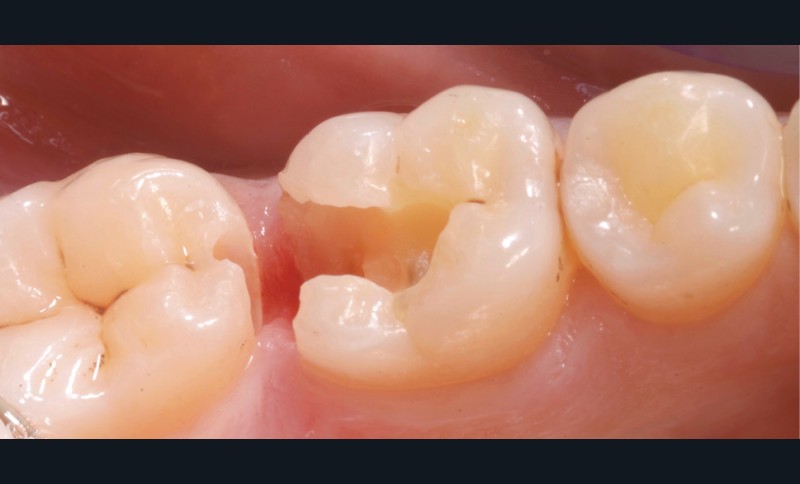

Lors de la préparation d’une cavité pour inlay/onlay, il est fréquent d’être confronté, en fin de nettoyage, à la présence d’une ou plusieurs parois résiduelles dont la résistance mécanique paraît douteuse du fait de leur localisation ou de leur épaisseur. Les parois épaisses (+ de 2 mm) peuvent généralement être conservées (cas clinique 1) et les parois fines (- de 1 mm) doivent généralement être recouvertes. Un inlay (en composite ou en céramique) est alors réalisé. Il doit avoir lui même, au final, une épaisseur globale minimale de 2 mm pour assurer sa résistance mécanique intrinsèque à la mastication. Si un recouvrement cuspidien est indiqué, la réduction occlusale doit donc se faire sur 2 mm de hauteur au minimum [1, 2].

Mais qu’en est-il des parois résiduelles d’épaisseur intermédiaire (entre 1 et 2 mm) (cas clinique 2) ?

S’il est impossible de connaître avec certitude le risque de fracture d’une cuspide, l’objectif de cet article est de donner des éléments objectifs de prise de décision de la conservation ou du recouvrement des parois d’épaisseur moyenne à la fin du nettoyage cavitaire selon la dent, l’occlusion, la forme et le volume de la cavité, la présence ou non de dentine, la vitalité ainsi que l’incidence esthétique.